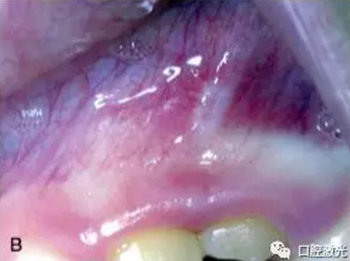

激光口腔潰瘍治療效果A:治療前,B:激光治療4天后